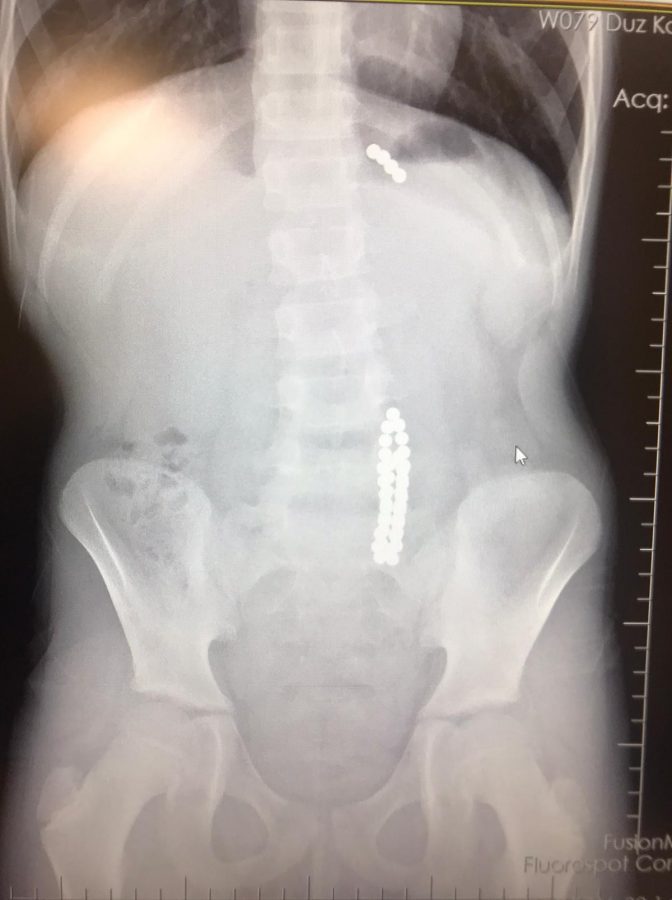

İstanbul Beylikdüzü'nde 9 yaşındaki bir çocuk ailesinin haberi olmadan neodyum adı verilen stres bilyeleri olarak da bilinen 42 adet mıknatısı yuttu. Birkaç gün sonra şiddetli karın ağrısı ve kusma şikayeti ile hastaneye gelen çocuğun röntgeni çekildi. Röntgen filminde çocuğun midesinde boncuklar halinde yabancı bir cisim tespit edildi. Bağırsağını delen cismi fark eden Beykent Üniversitesi Çocuk Cerrahisi Uzmanı Prof. Dr. Ali Çay çocuğu ameliyata aldı. Yapılan ameliyatta çocuğun bağırsaklarından rengarenk şekilde 42 adet neodyum çıkarıldı.

Konuyla ilgili konuşan Prof. Dr. Çay, yutulan cisimlerin normalde sindirim sistemi ile çıkabileceğini ancak çoklu mıknatısların bağırsaklarda delinmeye neden olabileceğini ifade ederek, "Bizim hastamız yaklaşık 42 tane bu mıknatıstan yutmuş çeşitli hastanelere müracaat etmiş. Burada yapılan incelemelerde çekilen filmlerde tesadüfen bu mıknatısları yuttuğunu biz radyografide gördük hastamızı ameliyata aldık. İnce bağırsak uç kısmında delinme oluşturmuştu. Biz bu mıknatısları çıkardık" dedi.